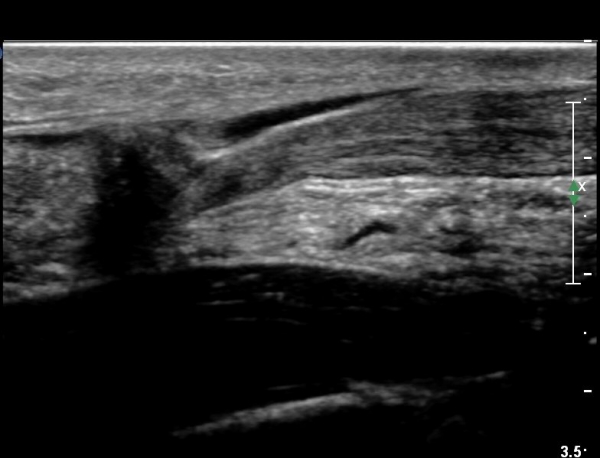

¾ÆÅ³·¹½º°Ç Á¾´Ü¸é°Ë»ç¿¡¼ ¾ÆÅ³·¹½º°Ç Àú¿¡ÄÚ ºÎÁ¾, ¿¬°á¼º ¼Ò½Ç, °ÇÁÖÀ§ ¼ö¾×Àú·ù ¼Ò°ßÀ» º¸ÀÓ(»çÁø 2, 3, 4, 5).